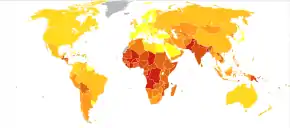

There have been studies showing the relationship between NTDs, folate deficiency and the difference of skin pigmentation within human populations across different latitudes. There are many factors that would influence the folate levels in human bodies: (i) the direct dietary intake of folic acid through fortified products, (ii) environmental agents such as UV radiation. In concern with the latter, the UV radiation-induced folate photolysis has been shown via in vitro and in vivo studies to decrease the folate level and implicate in etiology of NTDs not only in humans but other amphibian species. Therefore, a protection against the UV radiation-induced photolysis of folate is imperative for the evolution of human populations living in tropical regions where the exposure to UV radiation is high over the year. One body natural adaptation is to elevate the concentration of melanin inside the skin. Melanin works as either an optical filter to disperse the incoming UV radiation rays or free radical to stabilize the hazardous photochemical products. Multiple studies have demonstrated the highly melanized integument as a defense against folate photolysis in native Americans or African Americans correlates with lower occurrence of NTDs in general.[26][27]

Neural tube defects resulted in 71,000 deaths globally in 2010.[51] It is unclear how common the condition is in low income countries.[52]

Prevalence rates of NTDs at birth used to be a reliable measure for the actual number of children affected by the diseases.[53] However, due to advances in technology and the ability to diagnose prenatally, the rates at birth are no longer reliable.[53] Measuring the number of cases at birth may be the most practical way, but the most accurate way would be to include stillbirths and live-births.[53] Most studies that calculate prevalence rates only include data from live-births and stillborn children and normally exclude the data from abortions and miscarriages.[53] Abortions are a huge contributing factor to the prevalence rates; one study found that in 1986 only a quarter of the pregnancies with an identified NTD were aborted, but that number had already doubled by 1999.[53] Through this data, it's clear that excluding data from abortions could greatly affect the prevalence rates. This could also possibly explain why prevalence rates have appeared to drop. If abortions aren't being included in the data but half of the identified cases are being aborted, the data could show that prevalence rates are dropping when they actually aren't. However, it is unclear how much of an impact these could have on prevalence rates due to the fact that abortion rates and advances in technology vary greatly by country.[53]

There are many maternal factors that also play a role in prevalence rates of NTDs.[53] These factors include things like maternal age and obesity all the way to things like socioeconomic status along with many others.[53] Maternal age hasn't been shown to have a huge impact on prevalence rates, but when there has been a relationship identified, older mothers along with very young mothers are at an increased risk.[53] While maternal age may not have a huge impact, mothers that have a body mass index greater than 29 double the risk of their child having an NTD.[53] Studies have also shown that mothers with three or more previous children show moderate risk for their next child having an NTD.[53]